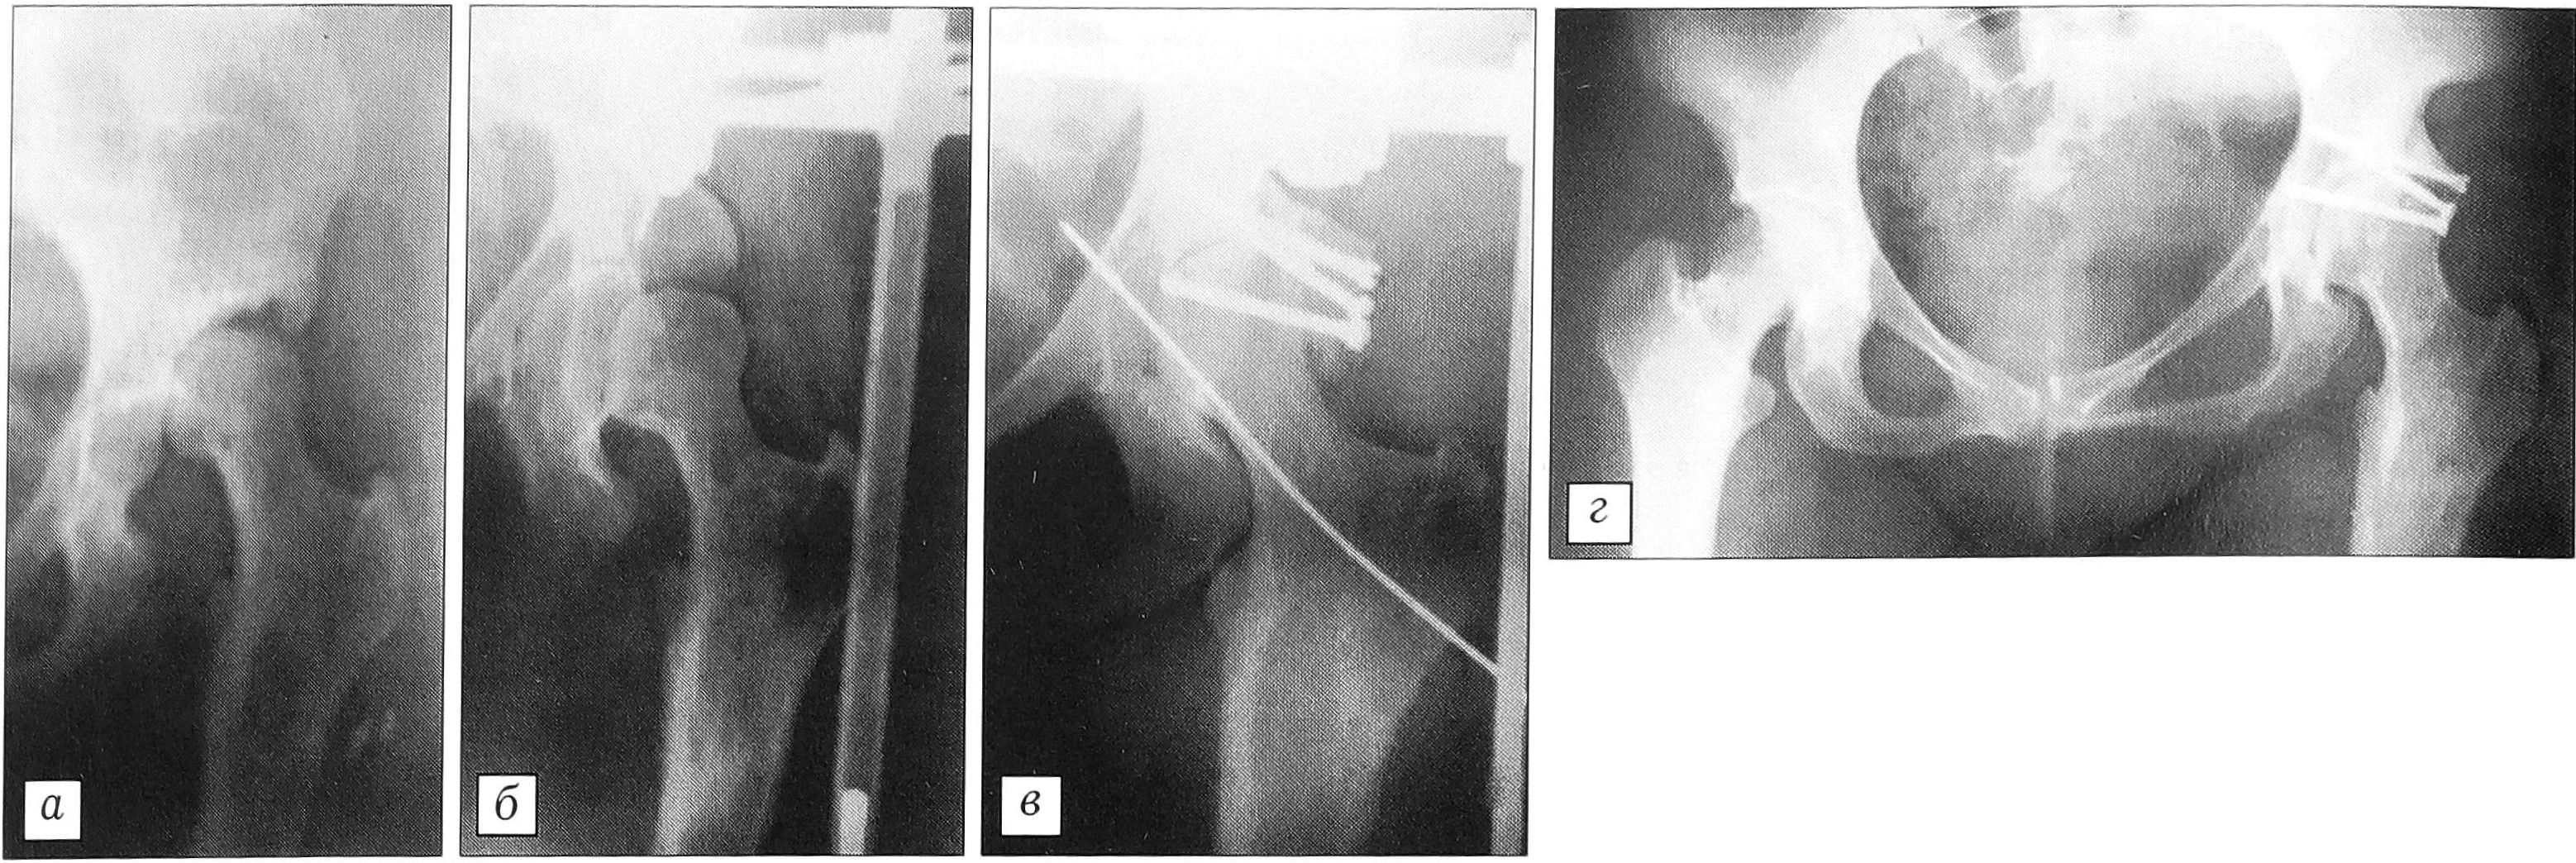

Рентгенограммы больной Р. 31 года. а — до начала лечения: патологический вывих бедра; б — на этапе дистракционного низведения бедра; в — после открытого вправления головки бедра с аутоостеопластикой задневерхнего края впадины; г — через 2 года.

09.09.99 выполнен первый этап операции — наложение анкерно-спицевого аппарата внешней фиксации «таз—бедро» (см. рисунок, б). Через 15 дней бедро было низведено до уровня вертлужной впадины. В этом положении внешняя фиксация продолжалась в течение 30 дней — до полной адаптации мышц бедра и околосуставных мягких тканей. 11.11.99 произведены открытое вправление головки бедра и аутопластика задневерхнего края вертлужной впадины трансплантатами, взятыми из крыла левой подвздошной кости (см. рисунок, в). Фиксация в аппарате продолжалась еще 5 нед. Операционная рана зажила первичным натяжением. Больная передвигалась при помощи костылей. Через 3 мес начала приступать на левую ногу. При обследовании через 2 года: пациентка ходит с опорой на трость, на рентгенограмме: форма вертлужной впадины и костные структуры сустава полностью восстановились (см. рисунок, г). От работы, требующей физической нагрузки, воздерживается. Приобрела новую профессию, не связанную с длительным хождением и подъемом тяжести. Наблюдение продолжается.